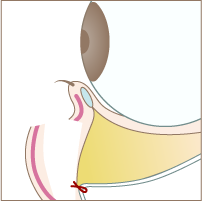

Step 03

隔膜と眼窩脂肪を一塊として引き下げ、骨膜に縫合します。

Step 04

切開した部分を縫合して完成です。

Step 03

隔膜と眼窩脂肪を一塊として引き下げ、骨膜に縫合します。

Step 04

切開した部分を縫合して完成です。